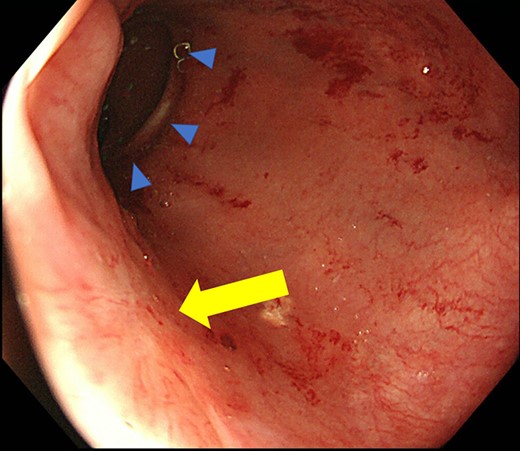

Case 1 was a 71-year-old man with a BMI of 29.7 kg/m2. Laparoscopic low anterior resection (LAR) and ileostomy was performed for rectal cancer in 2017 years. Postoperative fever and lower abdominal pain were noted, and colonoscopy was performed, and anastomotic leakage was noted with a correction of about 1/2 around the 6 o’clock direction of the anastomotic region, and fistula and formation of a large abscess cavity. After identification (Fig. 1), a tube was inserted for drainage and conservative treatment was performed. The patient was discharged on POD 46. Four months after the operation, marked improvement in the abscess cavity was noted but still remained (Fig. 2a and b). Anastomotic leakage was almost improved by colonoscopy at 17 months after surgery, but at the preference of the patient we performed colostomy 22 months after surgery (Fig. 3). It took a long time to improve intestinal movement of the colon because the large intestinal tract had not been used for a long time, and conservative treatment was performed using a nasogastric tube for paralytic ileus. Diet was initiated 7 days after surgery, and the patient was discharged from the hospital 14 days after surgery. The Wexner score [2] was 19 points one month after closure, 17 points 3 months after the operation and 16 points after 6 months after the operation, and severe anal dysfunction was observed, but gradually improved.

Colonoscopy shows that the suture failure has improved with only a slight depression.